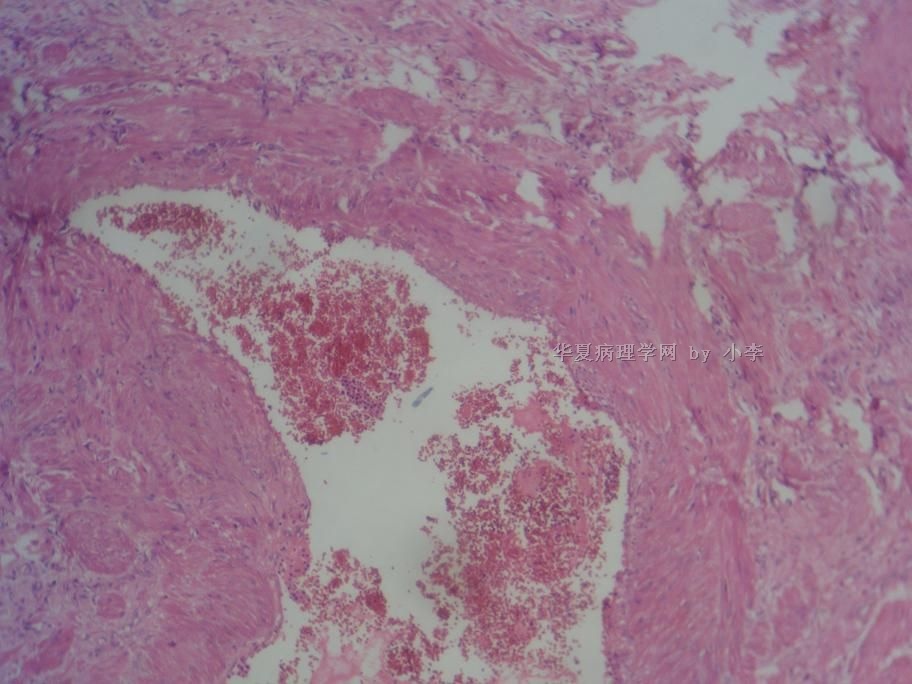

睾丸炎?

• 睾丸炎?图2

图2

首先考虑精子肉芽肿

慢性肉芽肿性炎

肉芽肿性睾丸炎

精子肉芽肿